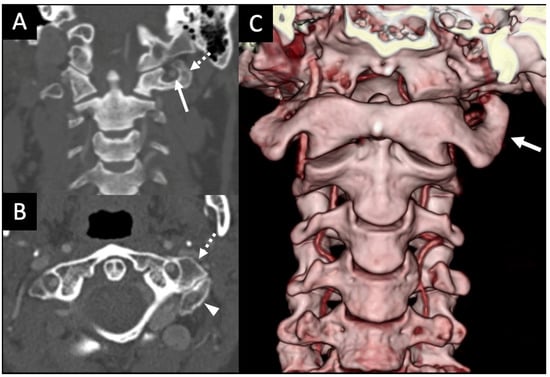

3.1. Variations in the V2 Segment

3.2. Variations of the V3 Segment